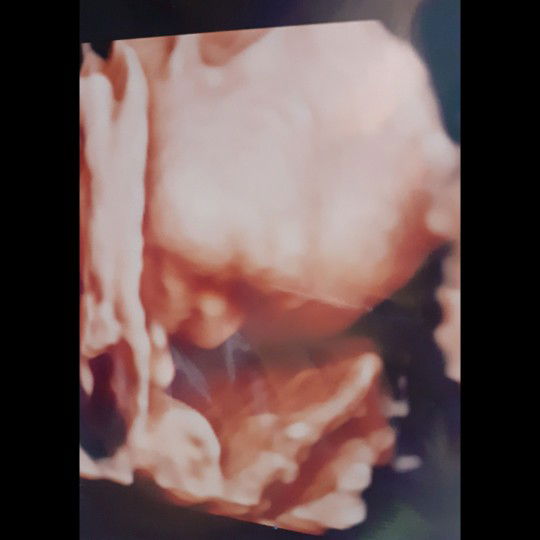

menginjak 9 bln